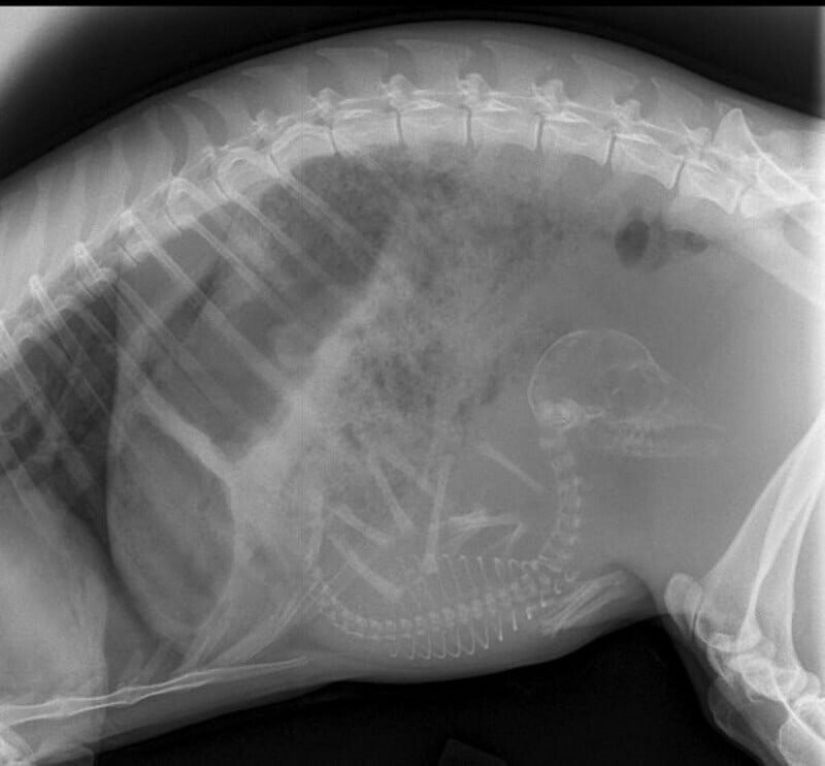

Quién vive en la casita: radiografías de animales preñados

Por Pictolic https://pictolic.com/es/article/quien-vive-en-la-casita-radiografas-de-animales-prenados.html¿Alguna vez te has preguntado qué sucede en el útero de una gata o una perra preñada? ¿Cómo encajan todos estos pequeños bebés allí y logran desarrollarse durante todo el embarazo? La mayoría de los animales preñados se examinan mediante rayos X. Y éstas, cabe señalar, son fotografías muy interesantes.

Especialistas que como parte de su trabajo observan animales que están listos para parir, compartieron estas sorprendentes imágenes de rayos X y ultrasonido.

gata preñada